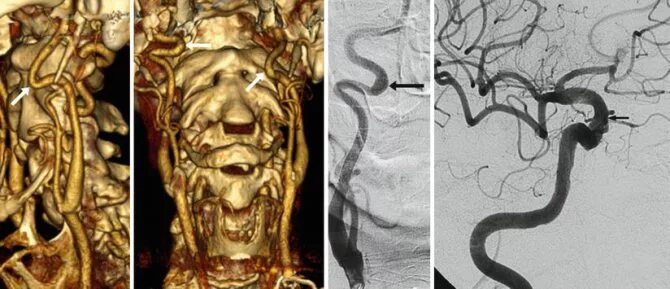

С образная извитость артерий